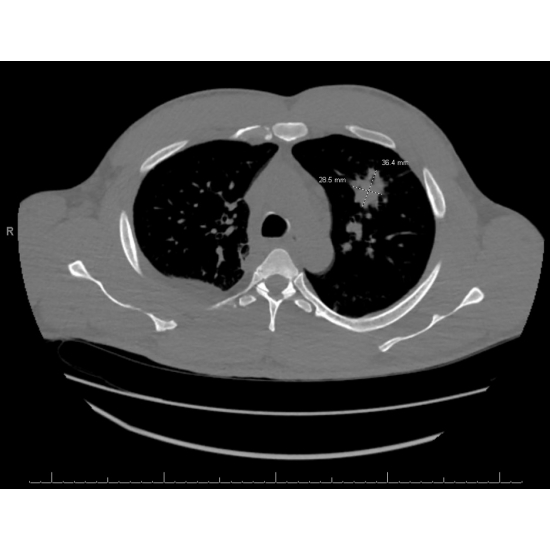

EKG demonstrated rightward axis and incomplete right bundle branch block. Echo found an EF of 60-65%, normal LV wall motion, moderate concentric LV hypertrophy, and mild to moderate dilation of the RV. Chest X-ray was notable for right pleural effusion, ill-defined airspace opacity in the left upper and mid lung zones, possibly an infectious/inflammatory process, cannot exclude neoplasm. Case Photo #1 CTA chest with contrast demonstrated 5.6cm x 5.4 mass causing severe narrowing of left upper lobe segmental pulmonary artery branches, as well as nodules. Case Photo #2 Thoracentesis was performed, and pleural fluid cultures were negative for growth, and cytology was negative for malignancy. Repeat CT chest with contrast done 11 days later showed a decrease in mass to 3.3 x 2.7 cm. Case Photo #3